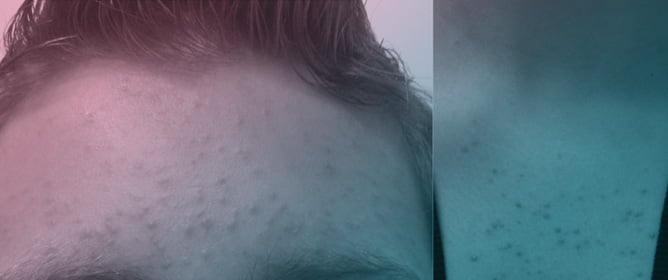

Malassezia Folliculitis: An Underdiagnosed Mimicker of Acneiform Eruptions -